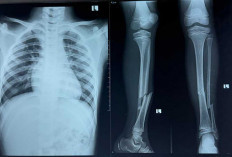

Abbad Atlet Cidera Parah Diturnamen PGRI Lubuk Linggau Tetap Optimis Bisa Jadi Pemain Bola Profesional

Biaya Pengobatan Abbad Puluhan Juta, Begini Penjelasan Orang Tua, Manager dan Panitia PGRI Lubuk Linggau